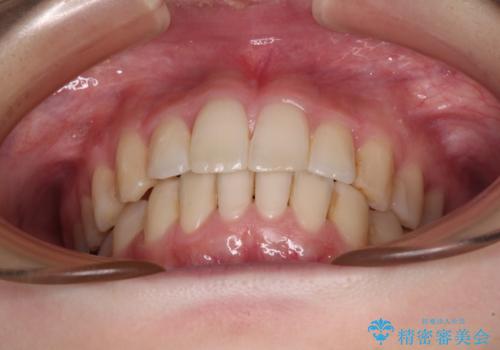

- 前歯のデコボコをクロスバイトを気にして来院された患者様です。

上顎骨の横幅が狭く、上下ともに内側に倒れ込んだ混み合った歯列となっていました。

左右ともに奥歯の咬み合わせには大きな問題がなく、窮屈な歯列を解決すれば歯列を整えることできたため、僅か1年で終えることができました。